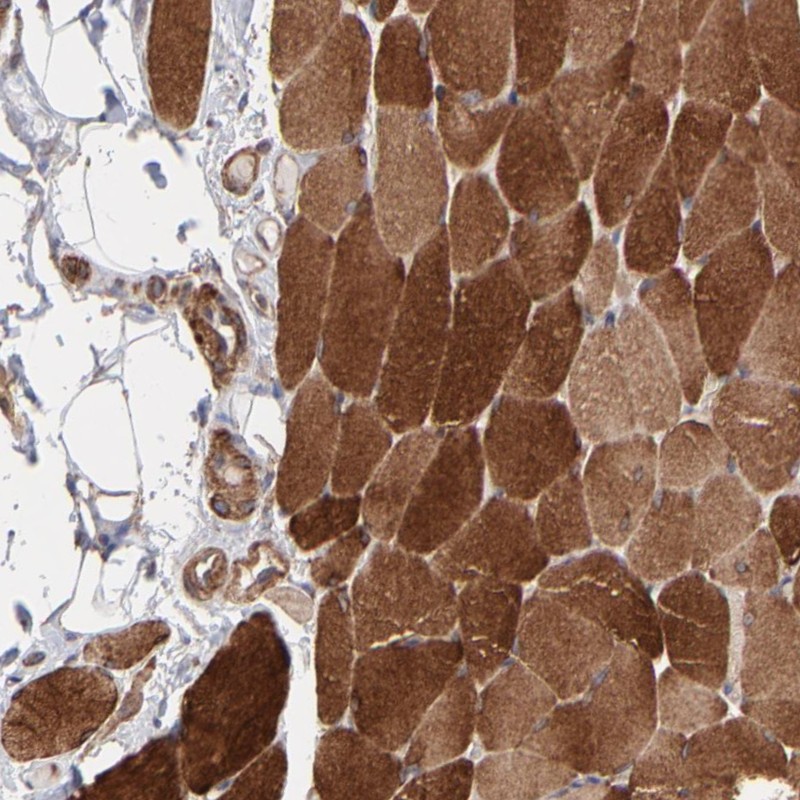

Immunohistochemical staining of human skeletal muscle shows strong cytoplasmic positivity in myocytes.